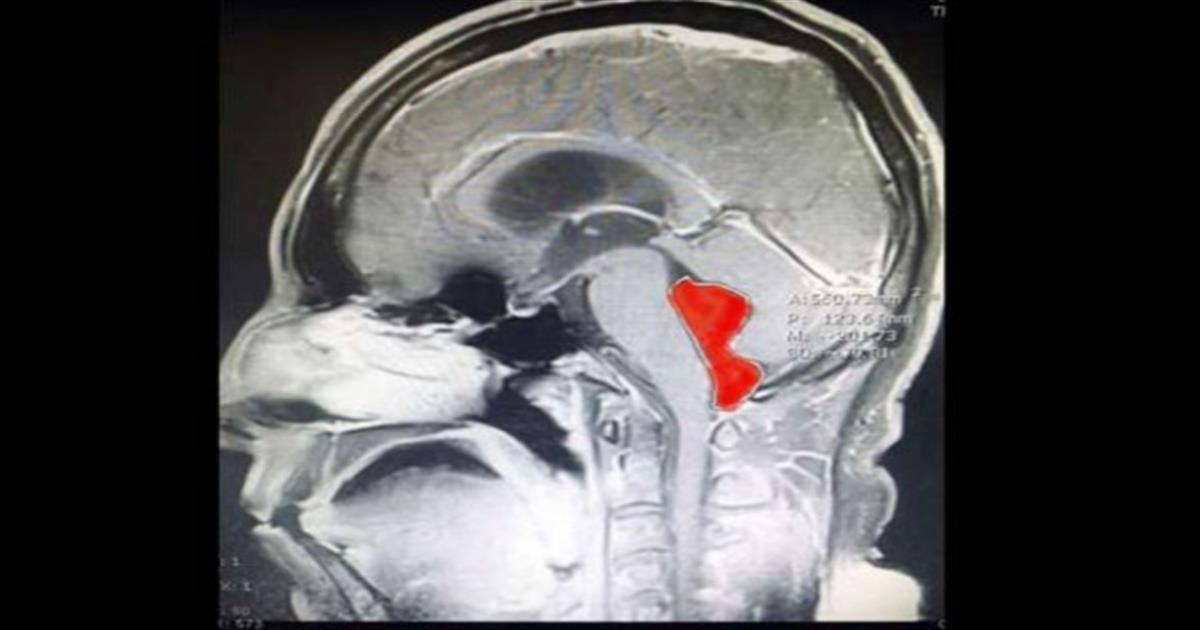

Η μαγνητική υπέδειξε μια κύστη στην τέταρτη κοιλία, πίσω από τον προμήκη μυελό και τη γέφυρα. Το ιατρικό team του κέντρου Ascension Seton του Τέξας ανάλαβε τη δύσκολη επέμβαση, καθώς η κύστη αποδείχτηκε τελικά πως ήταν το παρασιτικό σκουλήκι ταινία, μήκους 4-5 εκατοστών.

Το οποίο ήταν εκεί «τουλάχιστον 10 χρόνια». Ο Dr Jordan Amadio του Ascension Seton θεωρεί πως η ταινία πέρασε από μολυσμένη με αυγά ταινίας τροφή στον εγκέφαλο του Gerard, όπως αναφέρεται ο ασθενής (χωρίς επίθετο).